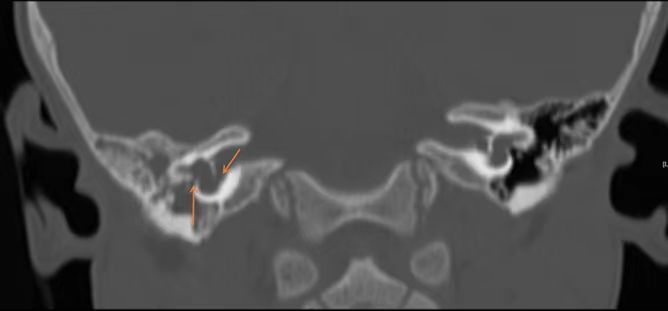

北京清华长庚医院耳鼻咽喉头颈外科副主任伊海金介绍,脑脊液耳漏是指脑脊液在颅内外压力梯度的作用下,从硬脑膜缺口及其所覆盖的颅骨缺损处经鼻腔、外耳道或开放伤口漏出的现象。这种“鼻涕”和普通鼻涕还不太一样,不粘稠,无色,更像清水。检查显示,患儿患有先天性内耳结构发育异常,不仅几乎无听力,言语发育受到影响,而且畸形的内耳与颅底相通,导致脑脊液自颅脑流入内耳、中耳、咽鼓管流到鼻腔,造成反复的鼻腔水样涕,过程中还导致感染,引发脑膜炎、吸入性肺炎等严重疾病。